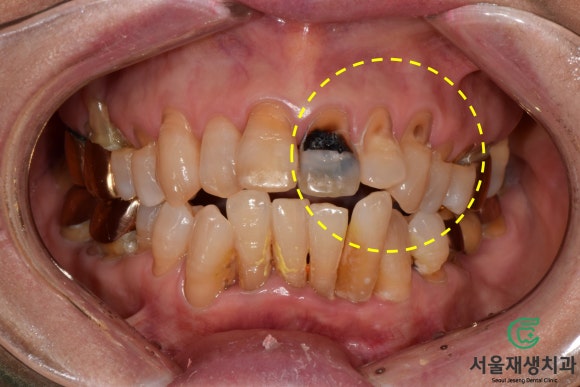

문제상황

잇몸 쪽으로 이가 패인지 오래됐는데

충치도 생겼어요ㅠ

큰 결심을 하고 내원해주셨습니다.

이가 마모된 틈으로

음식이 많이 끼고

보기에도 안좋았을 것 같은데...

오랜 세월을 참다~참다

큰 맘 먹고 귀한 걸음해주셨습니다.

치료 전 후 비교

신경치료 없이 레진만을 이용해서

치아의 심미성과 기능을 모두 얻어낸 사례입니다.